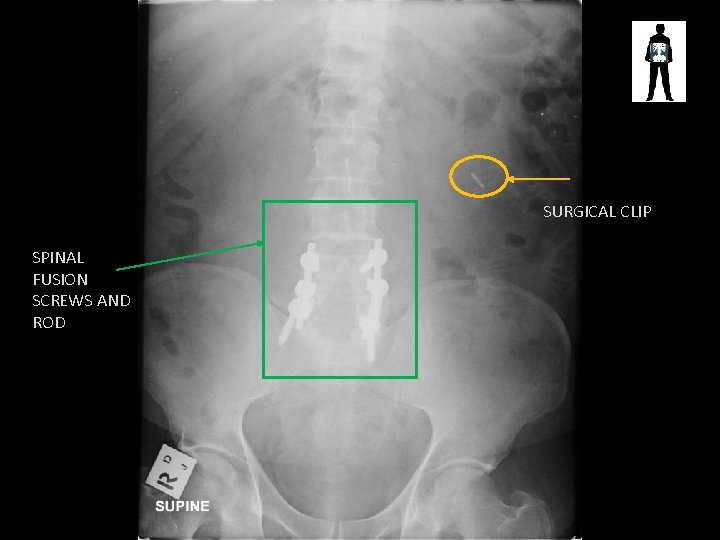

SURGICAL CLIP SPINAL FUSION SCREWS AND ROD